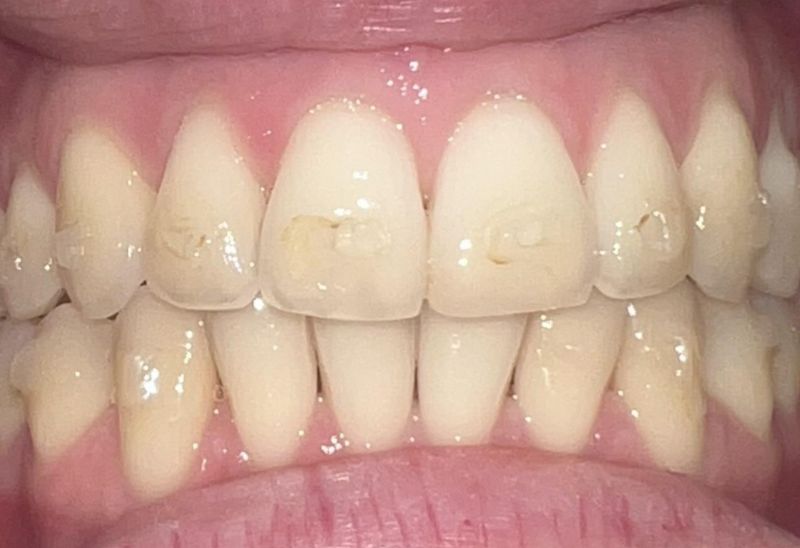

Prima e dopo l'apparecchio invisibile

In questa sezione mostreremo risultati reali ottenuti con l’ortodonzia invisibile a Roma. I cambiamenti riguardano non solo i denti, ma anche l’armonia del viso, la postura orale e l’autostima.